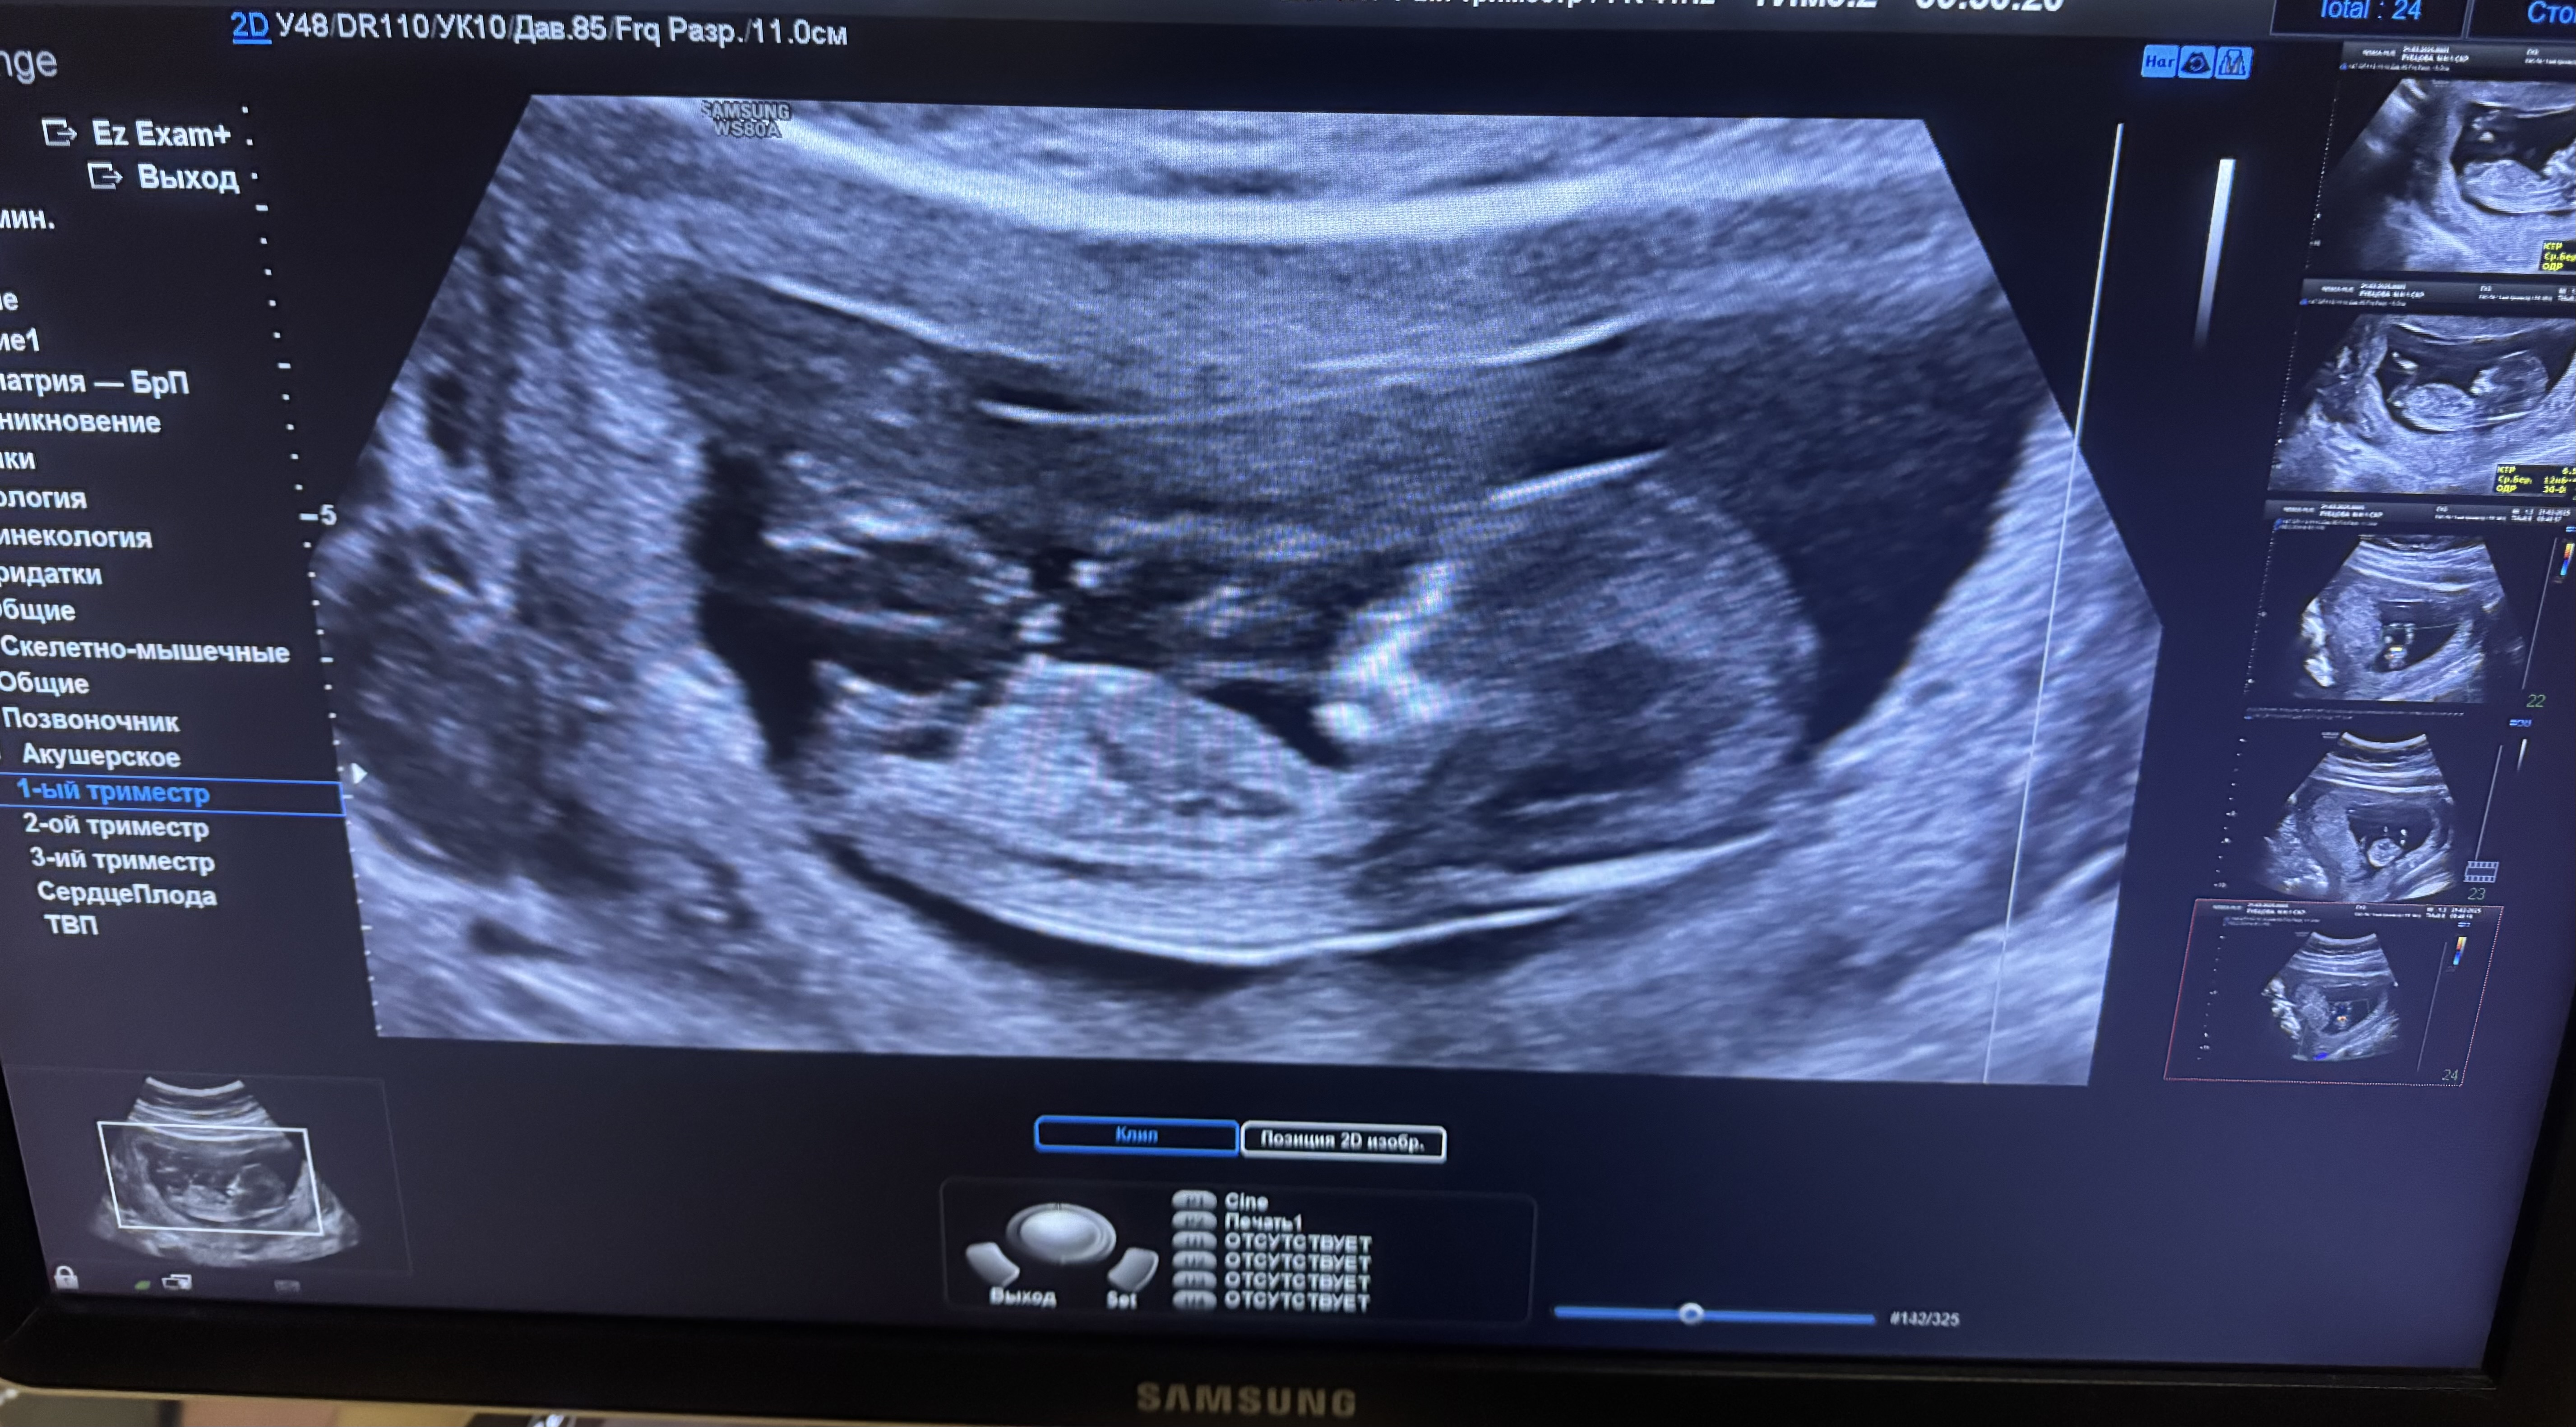

Скрининг 2. Нарушен кровоток в правой маточной артерии. ПИ 2,11

Девочки привет, вот вчера была на втором скрининге. По всем параметрам малыш соответствует. Все вроде хорошо.

Но доплер показал что нарушен кровоток правой маточной артерии🫤